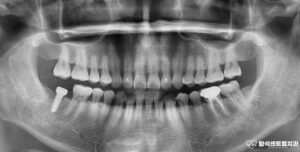

의정부 용현동 치과 : 신경치료가 되어있는 앞니 뿌리 부러짐, 발치 후 임플란트 즉시 식립 & ISQ 측정

안녕하세요. 의정부 용현동 치과 의사 곽승원입니다. ​ 치아의 뿌리가 부러지는 이유로는 스포츠 활동 시 공이나 다른 물체에 맞거나, 넘어지면서 바닥에 얼굴을 부딪히는 경우가 있습니다. ​ 또한 딱딱한 음식을 먹다 갑자기…